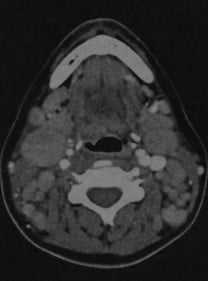

Лимфаденит шейный. КТ в горизонтальной проекции: увеличенные лимфатические узлы с образованием центральных полостей. Края лимфатических узлов нечеткие, кзади от левой яремной вены и медиальнее грудино-ключично-сосцевидной У мышцы определяется кольцо усиления.